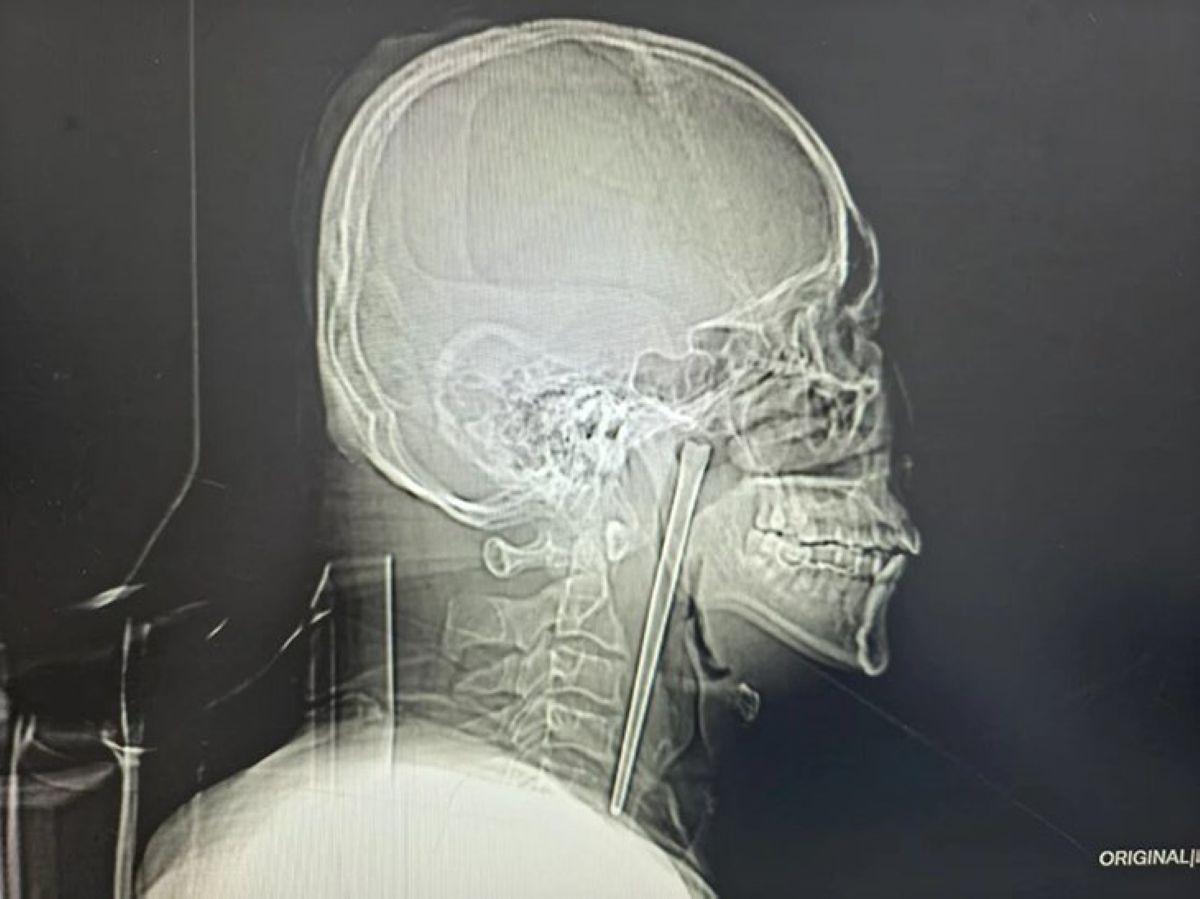

Υπάρχουν ιατρικά περιστατικά που ξεπερνούν κάθε φαντασία και η ιστορία του 46χρονου κ. Wang από την πόλη Dalian της Κίνας είναι σίγουρα ένα από αυτά. Ο άνδρας κατάφερε να επιβιώσει και να συνεχίσει την καθημερινότητά του για οκτώ ολόκληρα χρόνια, έχοντας μια μεταλλική ράβδο μήκους 12 εκατοστών σφηνωμένη στον λαιμό του.

Όλα ξεκίνησαν πριν από οκτώ χρόνια, όταν ο κ. Wang κατάπιε κατά λάθος ένα μεταλλικό chopstick ενώ έτρωγε. Αν και οι λεπτομέρειες παραμένουν ασαφείς, αναφορές από το νοσοκομείο υποδηλώνουν ότι η υπερβολική κατανάλωση αλκοόλ ίσως έπαιξε ρόλο στο αλλόκοτο ατύχημα.

Παρά την αίσθηση πνιγμού και την ενόχληση, ο ασθενής δεν αντιμετώπισε τότε δυσκολία στην αναπνοή. Όταν οι γιατροί τον ενημέρωσαν ότι η αφαίρεση απαιτούσε μια ριψοκίνδυνη χειρουργική επέμβαση με πλάγια τομή στον αυχένα, ο Wang πήρε μια απίστευτη απόφαση: αρνήθηκε το χειρουργείο και επέλεξε να ζήσει με το αντικείμενο μέσα του.

Όταν τα παυσίπονα έπαψαν να δρουν, ο Wang επισκέφθηκε το Κεντρικό Νοσοκομείο του Τεχνολογικού Πανεπιστημίου Dalian. Η ακτινογραφία άφησε τους γιατρούς άφωνους: το chopstick ήταν σφηνωμένο στον λαιμό του σαν βέλος, αποτελώντας μια «ωρολογιακή βόμβα» για τα γειτονικά αιμοφόρα αγγεία.